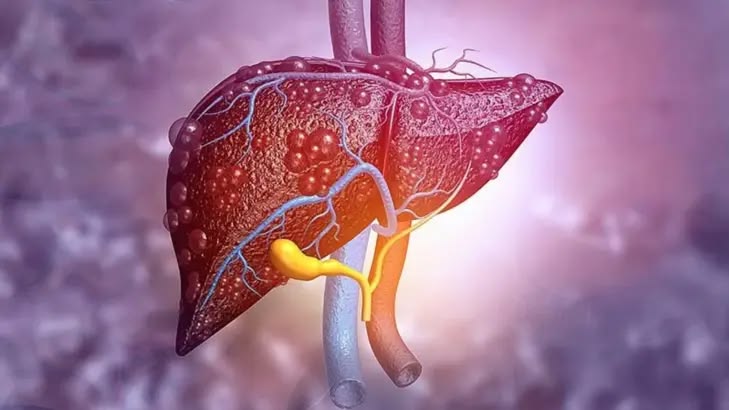

احذر هذه المشروبات إذا كنت مصابًا بمرض الكبد الدهني

لا يقتصر تأثير مرض الكبد الدهني على الأطعمة فقط، بل تشمل المخاطر بعض المشروبات أيضًا. فهناك مشروبات تعزز صحة الكبد، وأخرى قد تزيد من تفاقم المرض.